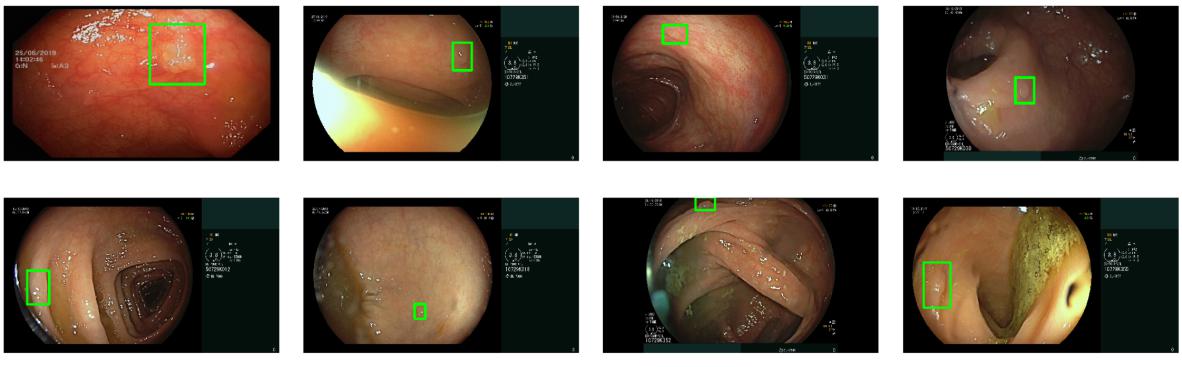

Das Standardverfahren für die Erkennung und Entfernung von Polypen ist die Darmspiegelung, bei der ein Gastroenterologe den Darm über eine Kamerasonde nach präkanzerösen Polypen untersucht.

In einer neuen Forschungsarbeit stellen Google-Forscher nun eine Bildanalyse-KI vor, die die Kamerabilder während der Darmspiegelung analysiert und Gastroenterologen hilft, Polypen zu identifizieren.

Das zweite KI-System sucht direkt in den Aufnahmen nach Polypen. Die Forscher haben die Bildanalyse-KI dafür mit Aufnahmen von 3.600 Untersuchungen oder 86 Millionen Bildern trainiert und anhand von Aufnahmen von 1.400 Untersuchungen getestet.

In den Tests erkannte DEEP (Detection of Elusive Polyps) 97 Prozent aller Polypen, darunter solche, die in den Testdaten von mehreren menschlichen Experten nicht erkannt worden waren. Waren die Polypen nur kurz im Bild zu sehen, erkannte DEEP noch 88,5 Prozent bei fünf Sekunden und 84,9 Prozent bei zwei Sekunden Sichtbarkeit.

Eine erste klinische Überprüfung fand in Kooperation mit dem Shaare Zedek Medical Center in Jerusalem statt: Dort unterstützte DEEP Gastroenterologen bei 100 Darmspiegelungen. Laut Google half das System im Schnitt, ein Polyp pro Untersuchung aufzudecken, der andernfalls unbemerkt geblieben wäre.

DEEP verfehlte darüber hinaus keinen Polypen, der menschlichen Experten ebenfalls auffiel und meldete nur 3,8 falsche Alarme pro Untersuchung. Laut der Forscher war das Feedback der Gastroenterologen durchgängig positiv. Weitere Kooperationen sollen folgen, um die Forschungsergebnisse zu validieren.